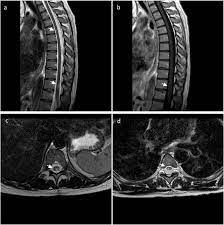

Transverse Myelitis Causes Symptoms Prognosis Treatment

Transverse Myelitis Causes Symptoms Prognosis Treatment from healthjade.net